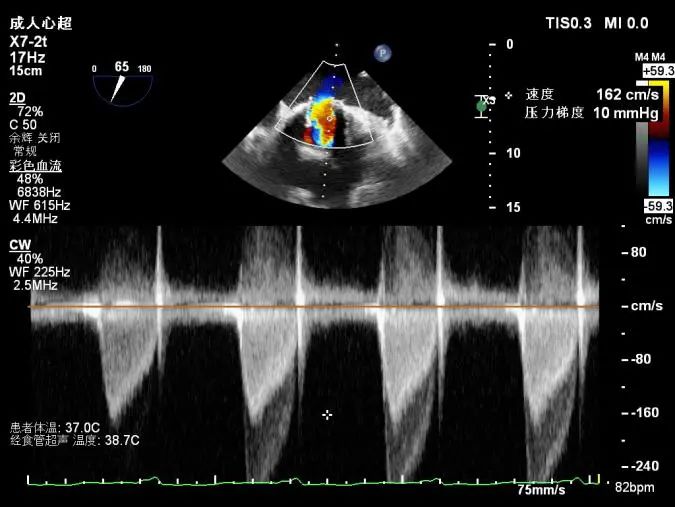

食道超声示:人工二尖瓣功能良好,无反流,封堵后瓣周反流基本消失。

术中及术后食道超声示:

术后食道超声

﹥TA-MVR ViV+PVL封堵术后:二尖瓣位生物瓣血流速度加快,原瓣周漏消失;

二尖瓣间隔侧探及封堵器1枚,位置固定,原生物瓣与室间隔间裂隙消失。

多普勒检查:二尖瓣位生物瓣舒张期峰值流速加快,平均跨瓣压差9mmHg,峰值跨瓣压差27mmHg,原瓣周漏消失。